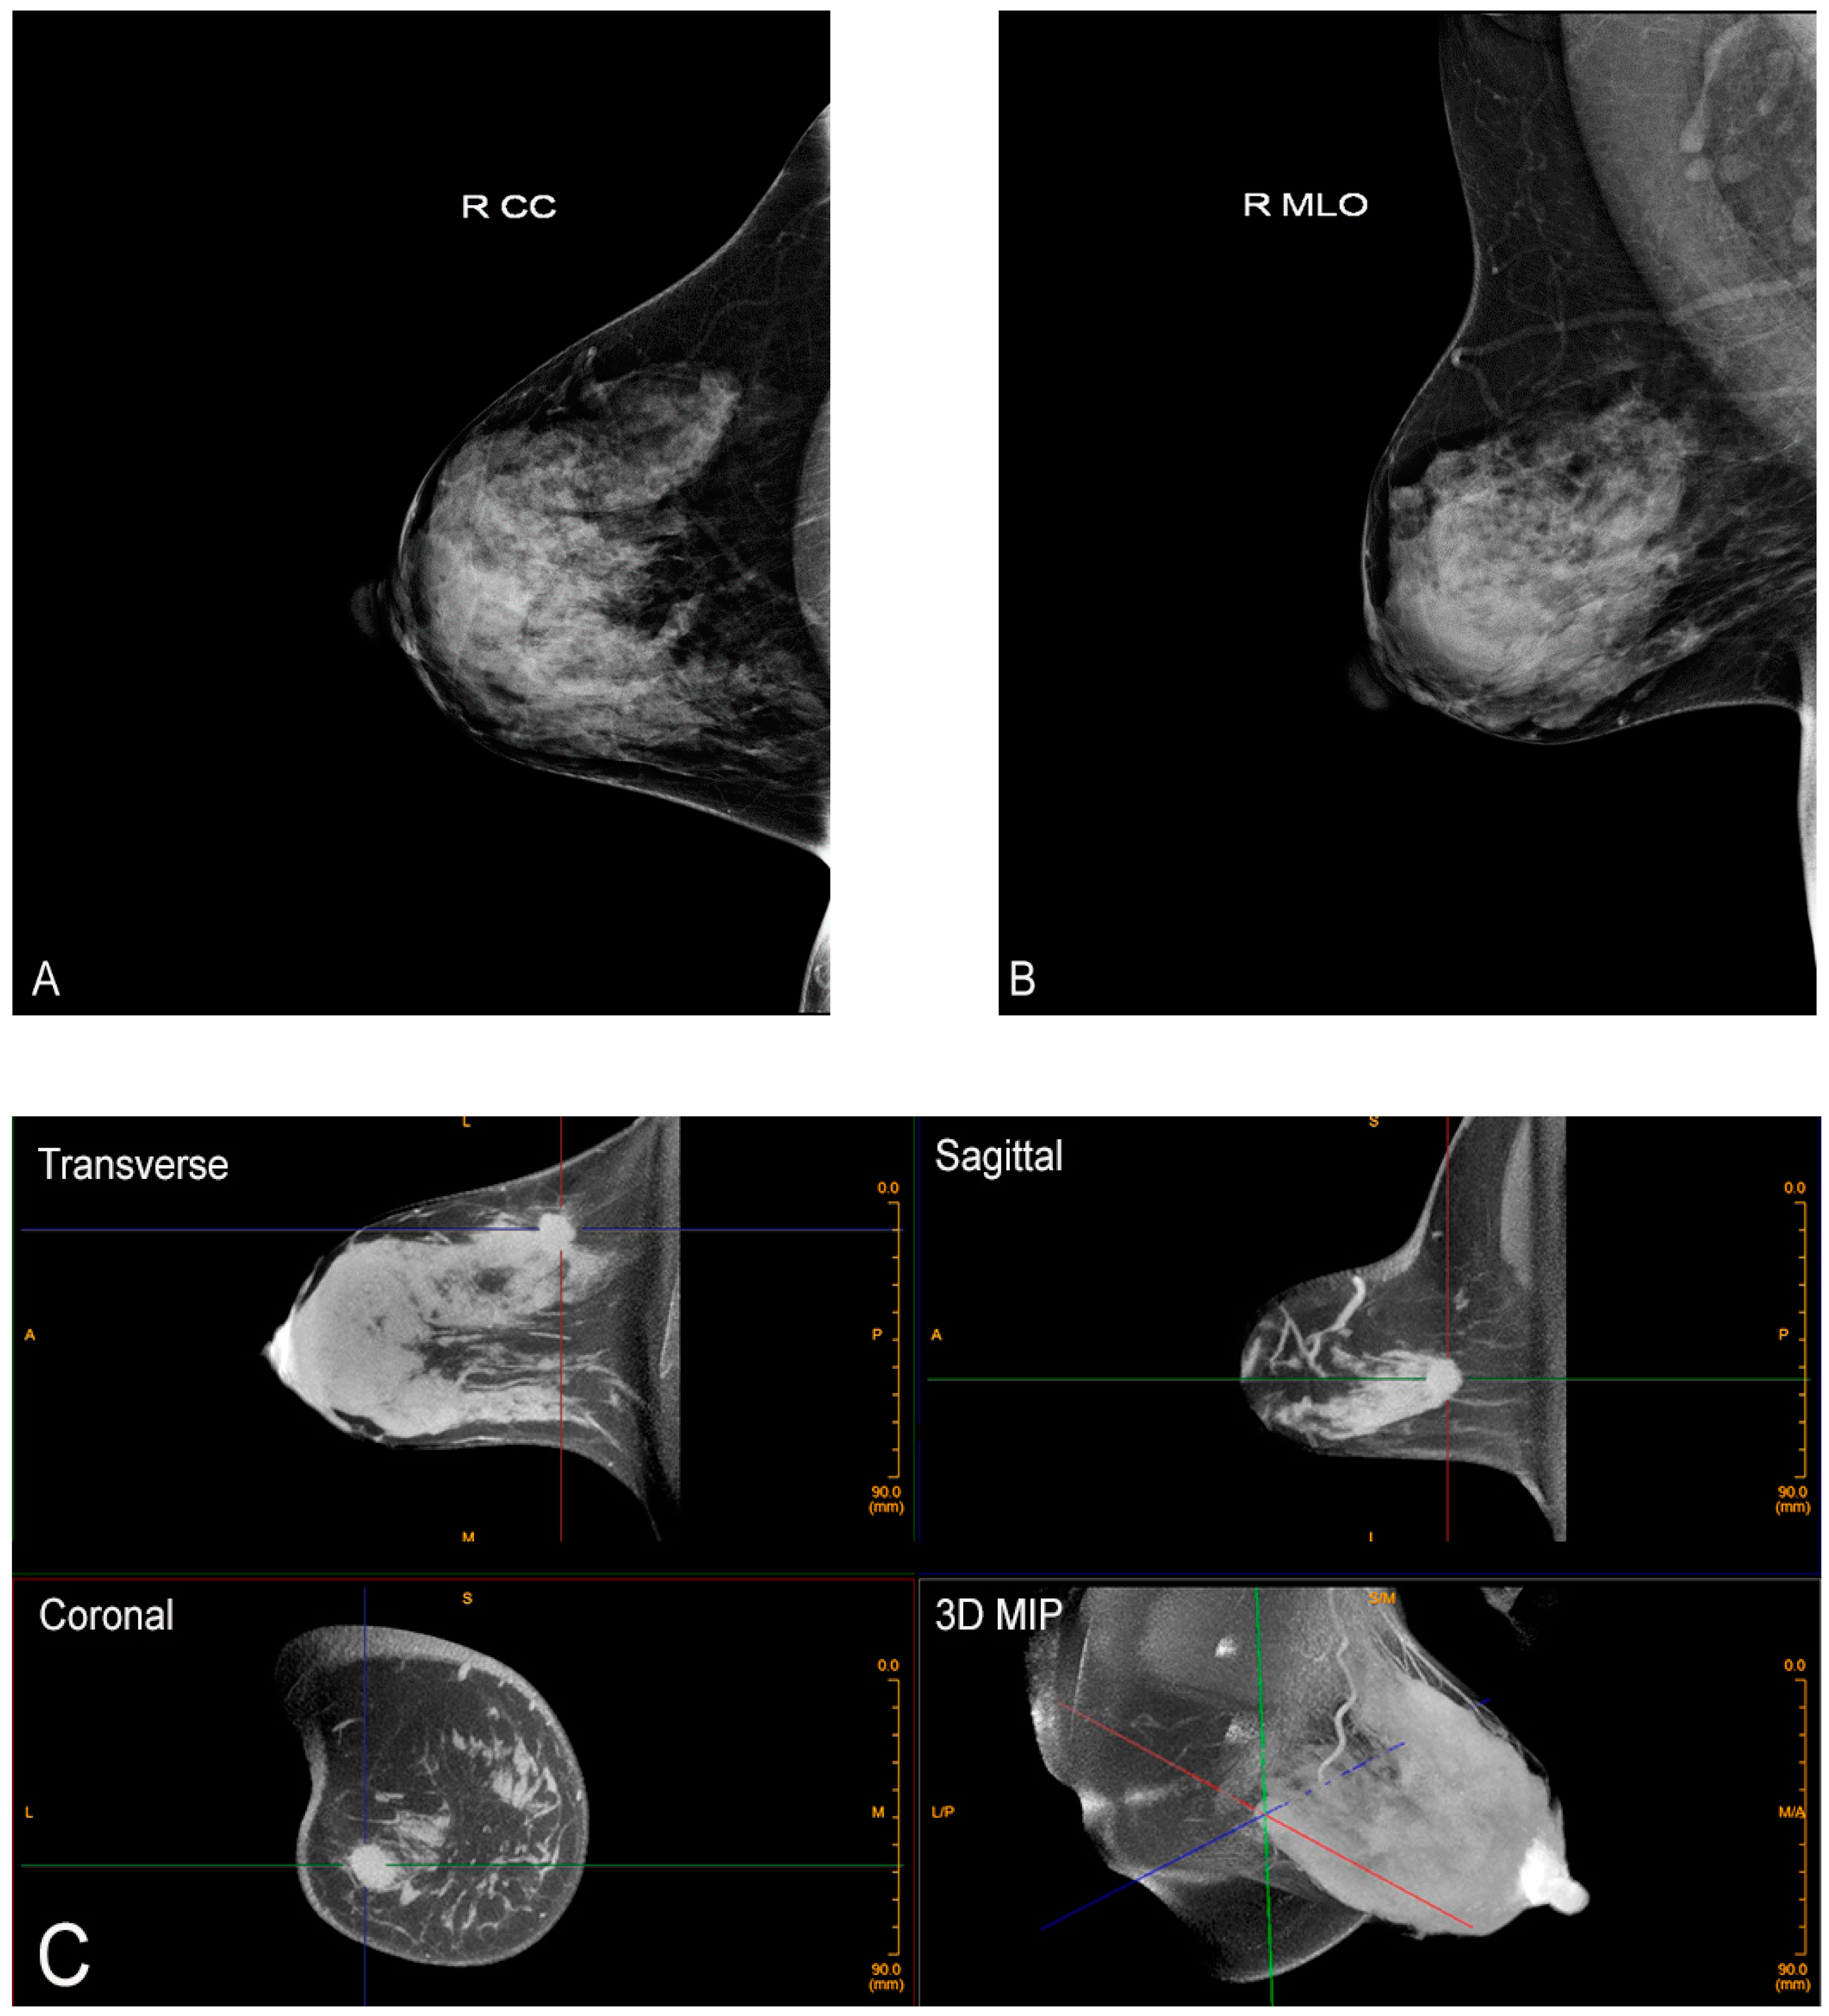

Figure 5.

Contrast-enhanced CBBCT. Left CC (A) and MLO (B) views demonstrate two masses (black and white arrows). (C) Contrast-enhanced CBBCT with gridlines marking the mass corresponding to the black arrow on mammography. (D) Contrast-enhanced CBBCT with gridlines marking the mass corresponding to the white arrow on mammography.